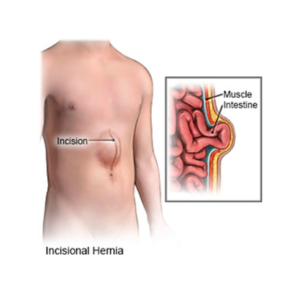

Incisional Hernia